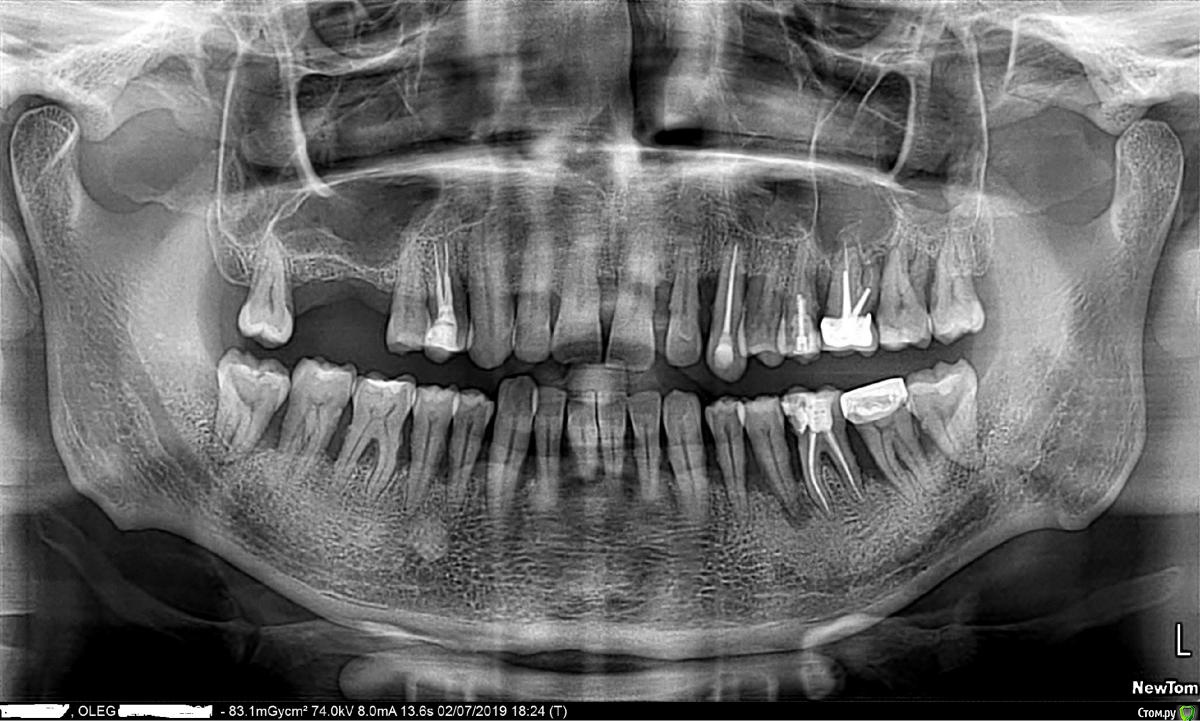

KOA45 Опубликовано 3 июля, 2019 Поделиться Опубликовано 3 июля, 2019 Добрый день уважаемые врачи ! Хочу заняться своими зубами.Тревожит подвижность зубов, есть свищ на пятерке. Просьба прокомментировать снимок .Какие варианты лечения, имплантация? Мне 45 лет , общее здоровье нормальное, лекарств ни каких не принимаю. Лет 10 назад, врач который ставил пломбу , посоветовал найти специалиста сделать лоскутную операцию с посадкой костных блоков, так как большая просадка кости. Конечно это не было сделано. Сейчас это наверное уже поздно? А если имплантация то какие варианты , и цены (можно в личку). Ссылка на комментарий

Bier Опубликовано 3 июля, 2019 Поделиться Опубликовано 3 июля, 2019 Ну самое простое - рассмотреть вариант все на 4х-6ти с удалением зубов. Ссылка на комментарий

Bier Опубликовано 3 июля, 2019 Поделиться Опубликовано 3 июля, 2019 восстановить - нет. побороться за зубы и прожить с ними еще несколько лет - да. Может и 10 лет. Но тогда в другую клинику нужно обращаться ) Ссылка на комментарий